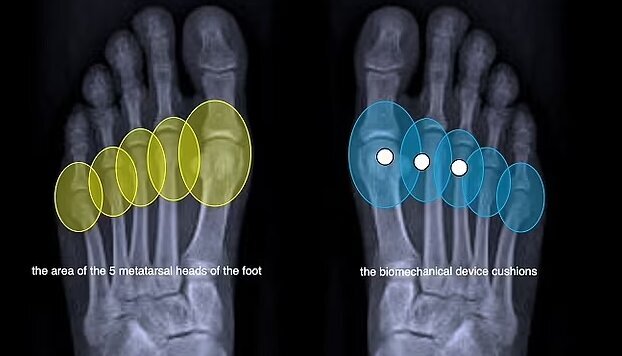

این کفی که توسط شرکت ایتالیایی «GAIT-TECH» ساخته شده است، ضربه را هنگام راه رفتن از بین میبرد و فشار را در سراسر پا پخش میکند. این کفی در دید نیست و به طور ناخوشایند زیر پا تکان نمیخورد.

کفشهای پاشنهبلند، تمام وزن کاربر را روی قسمت جلوی پا قرار میدهند و فشار شدیدی را بر انتهای استخوانهای کف پا و مفاصل بین انگشتان و پا وارد میکنند. این امر به افزایش خطر شکستگی استخوان، ضخیم شدن بافت اطراف عصب پا و سایر آسیبهای احتمالی منجر میشود.